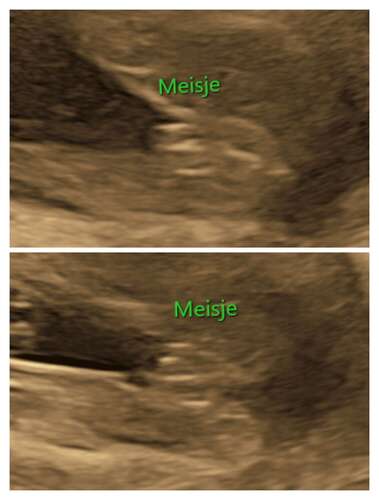

Bij ons dochtertje was het ook best lastig. Daar stak het ook nog best uit bij 1 echo (bovenste). Daardoor twijfelde ik best wel. Maar door de onderste was het best duidelijk. En nubster heeft me ook gerustgesteld dat de vk het echt wel goed had😅

Ja ! Zeker een meisje

@Peterpan, in het vorige deel gaf je aan, (zowel nub als pottyshot) dat ons kindje een meisje is. Je had gelijk! :) echo gehad met 15 weken en 3 dgn. Het is een meisje volgens de echoscopist!